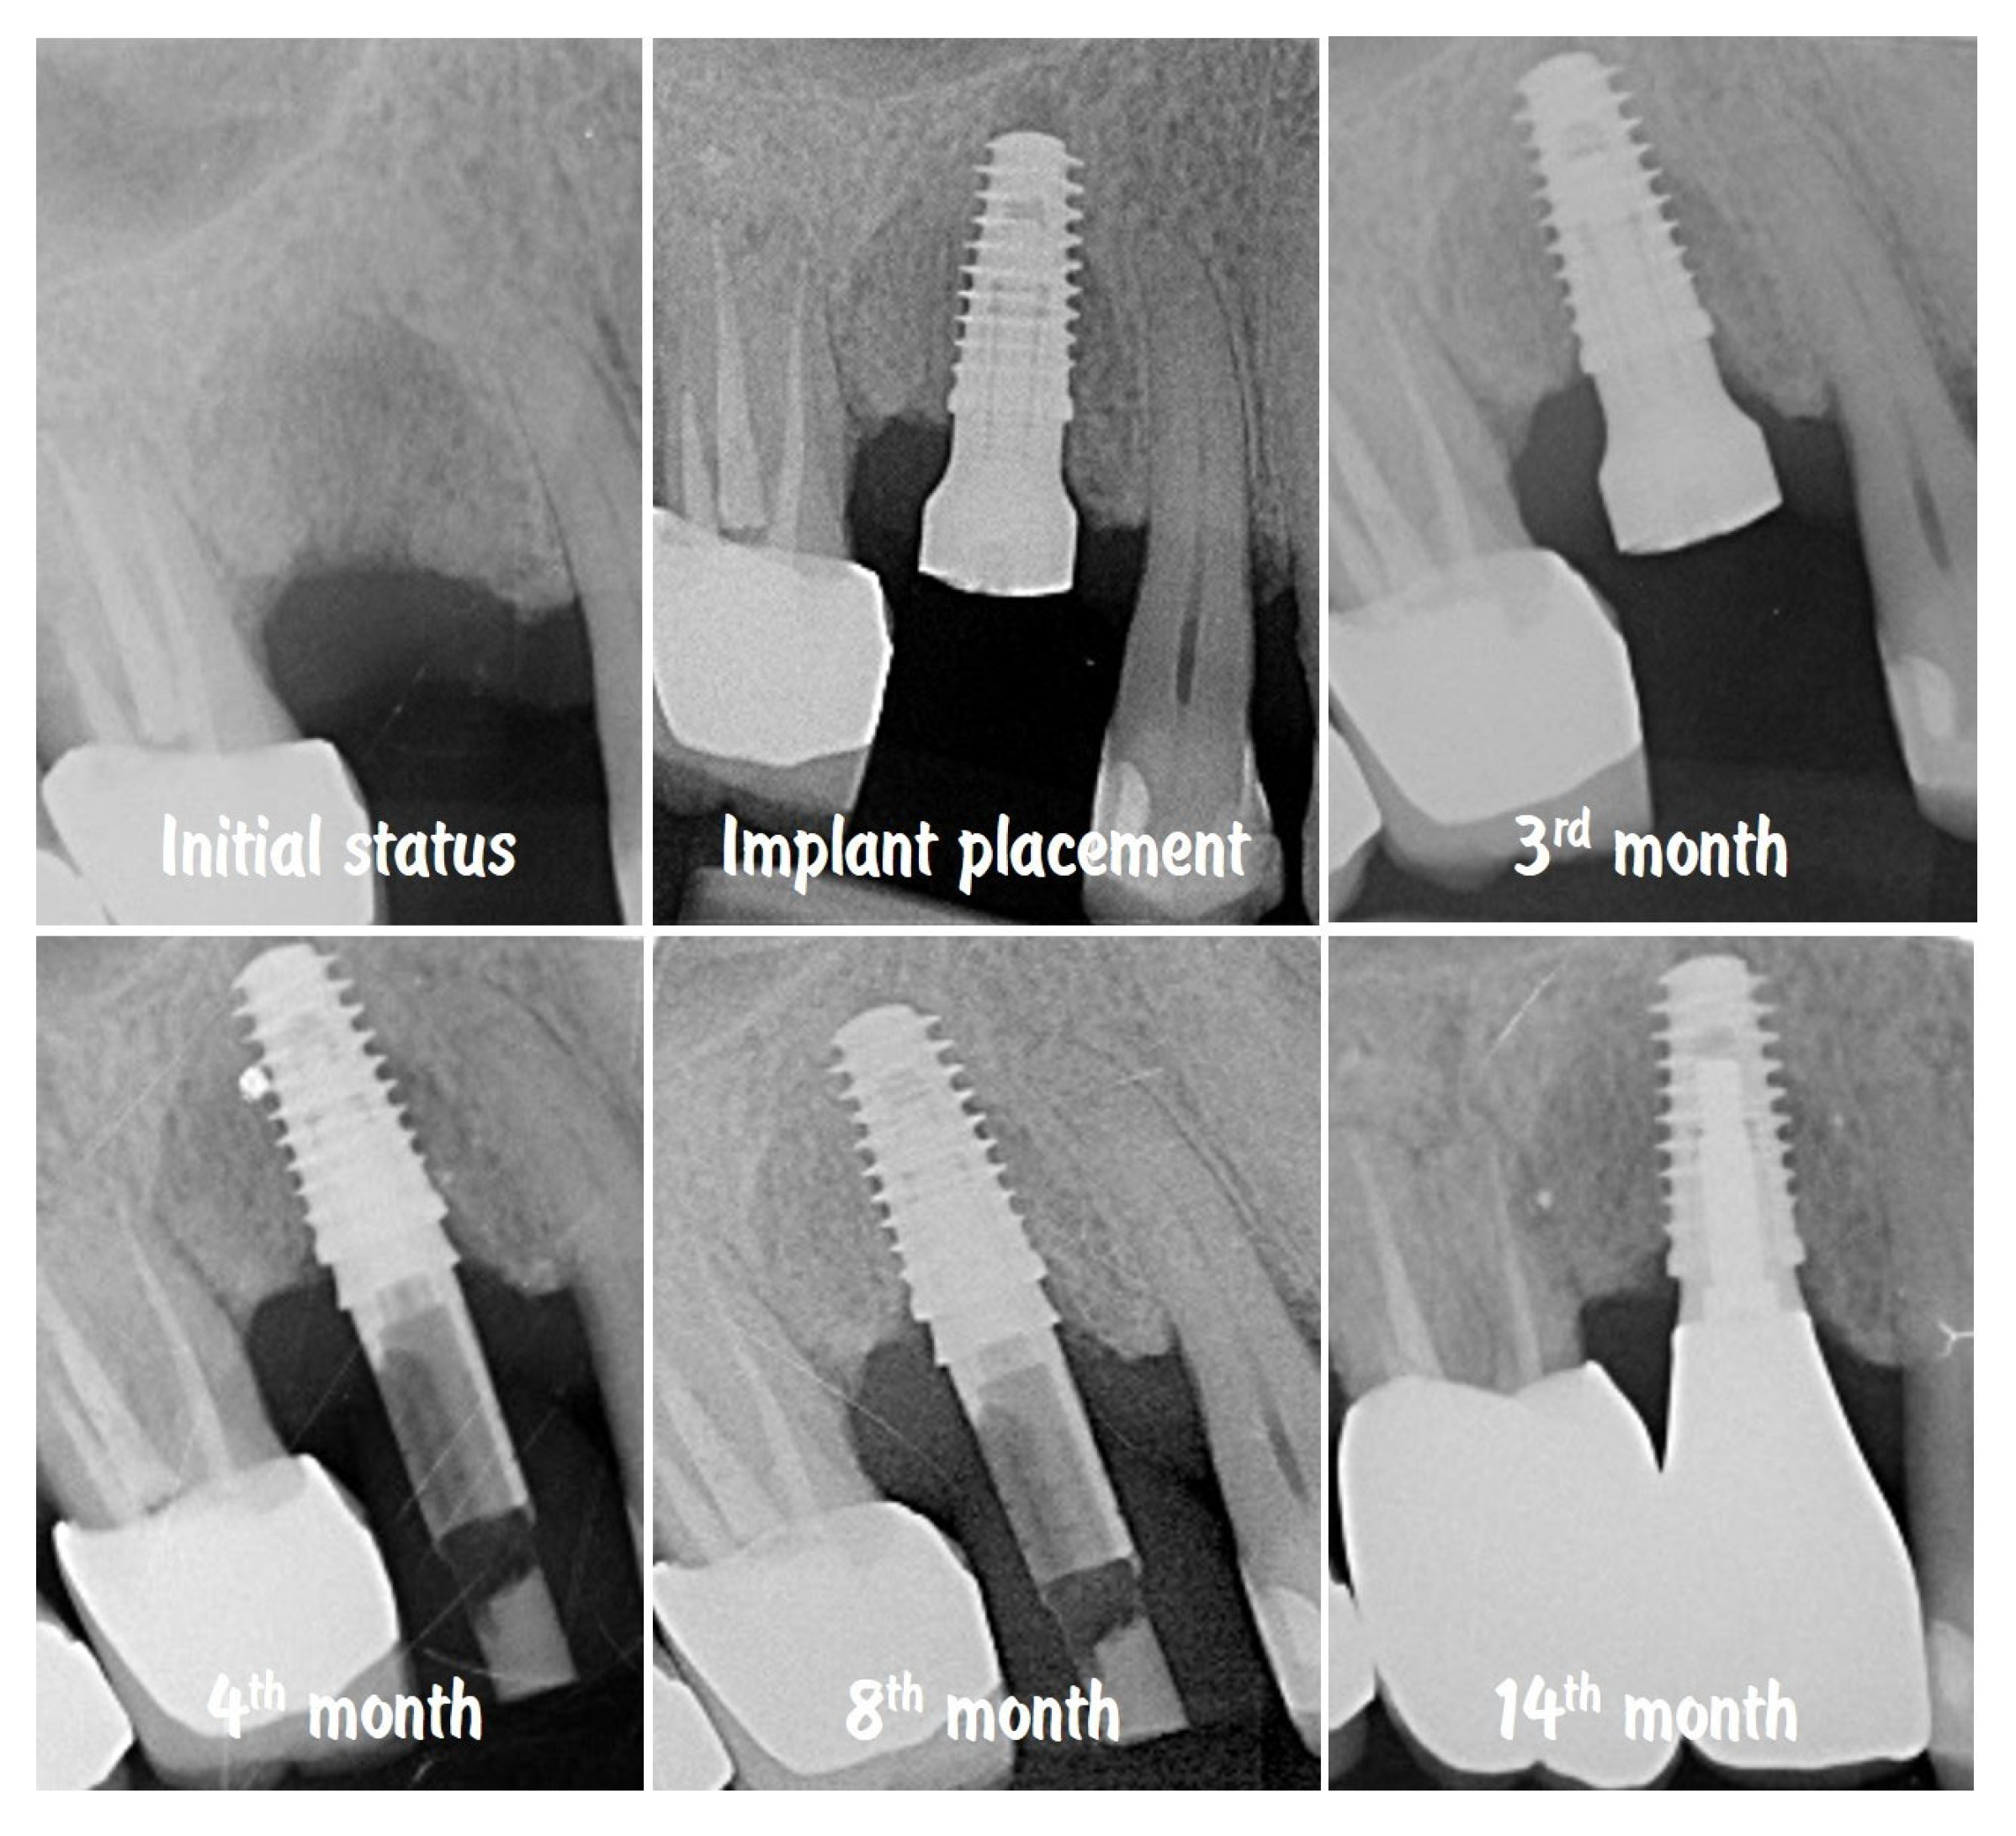

| Timepoint | Horizontal Thickness (mm) | Vertical Thickness (mm) | Clinical/Radiographic Findings | |

|---|---|---|---|---|

| 1 | Baseline (Day 0) | 2.3 | 2.4 | Initial thin buccal tissue |

| 2 | 2 weeks post-op | Uneventful healing, stable mucosal margin | ||

| 3 | 3 months post-op (with provisional) | 3.4 | 3.4 | Increased thickness, stable bone and mucosa |

| 4 | 4 months post-provisional | 3.5 | 3.6 | Stable peri-implant mucosa around provisional crown |

| 5 | 8 months post-op (final crown) | 3.5 | 4.1 | Final crown placed, harmonious soft tissue contours, and stable crestal bone |

| 6 | 14 months post-definitive | Long-term stability of soft tissue and crestal bone confirmed |